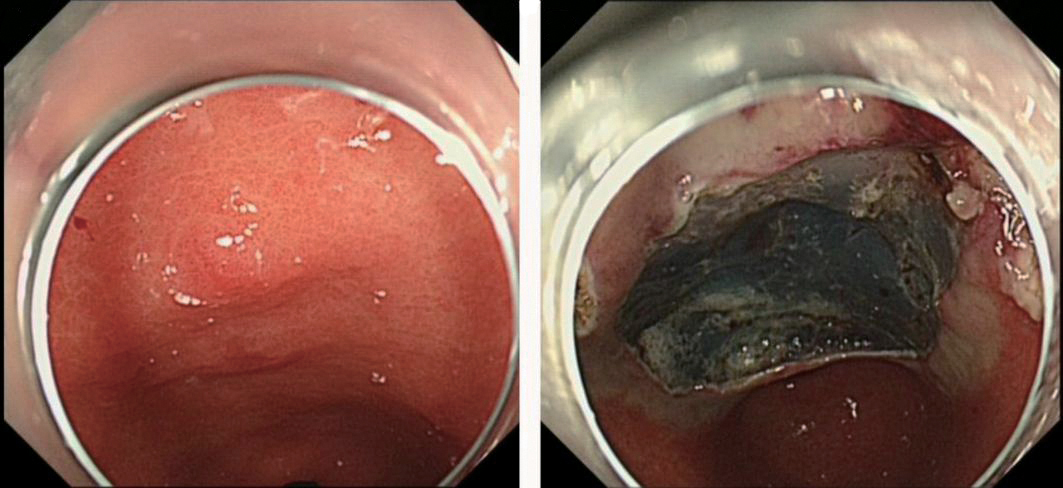

1.针对肠息肉摘除术后出血的应用

患者男,48岁,升结肠息肉EMR切除术后,术后反复出血,经2次内镜下钛夹夹闭止血后再次出血,第3次进行内镜下止血粉治疗后成功止血,见图1

图1 肠息肉摘除术后止血

A:升结肠处原氩离子凝固术处出血;B:创面予以钛夹缝合,予以复合微孔多聚糖止血粉喷洒;C:创面止血完成